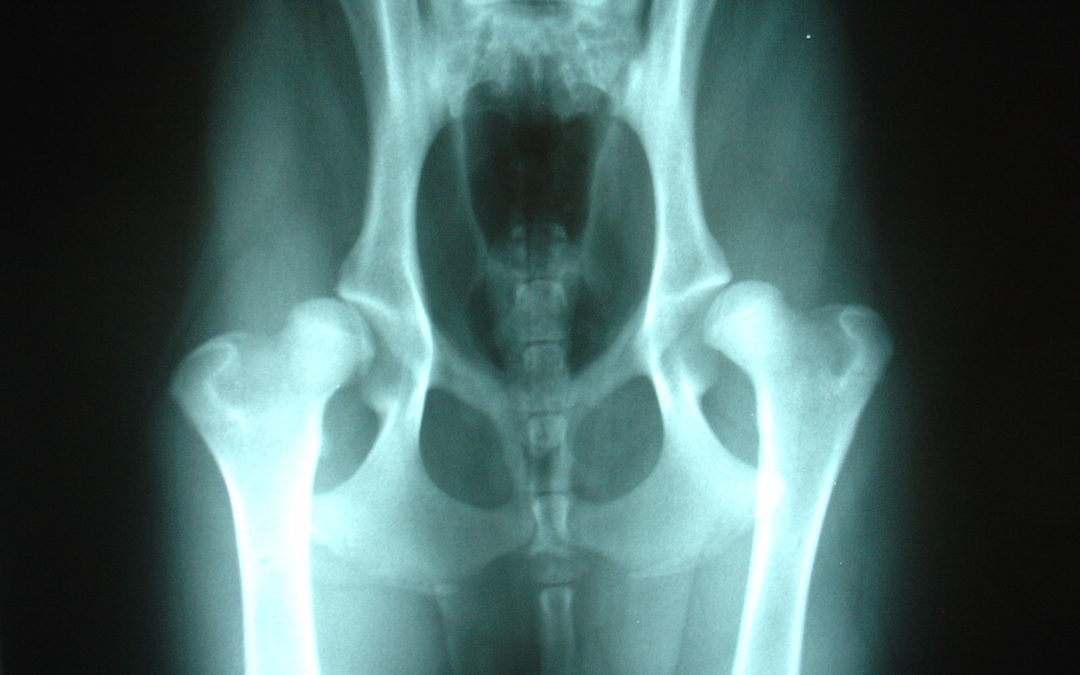

Displasia coxo-femural

A Displasia Coxofemoral (DCF) é uma doença poligênica (vários genes relacionados a formação de estruturas) de natureza multifatorial e extremamente complexa, que comumente resulta em alterações degenerativas irreversíveis devido a incongruência articular que leva à...